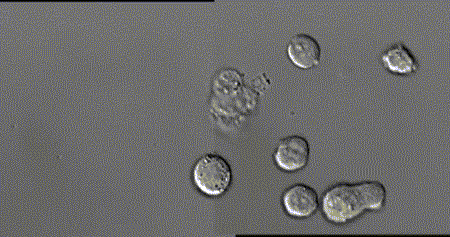

每个细胞毒性T细胞大约是人类头发直径的十分之一,它们在人体内不断巡逻,找出并杀死癌细胞或感染了危险病毒的细胞。

当T细胞(绿)发现癌细胞(蓝)时,通过分泌的毒素附着在癌细胞上,来检测、分辨正常细胞与癌细胞。